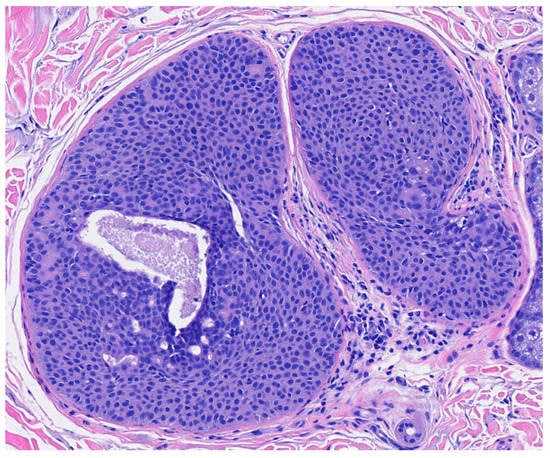

Poroma variants are differentiated based on the predominant cell type present and the degree of epidermal/dermal involvement [2]. However, multiple variants can exist within the same lesion. DDTs are primarily confined to the superficial dermis and are composed of small solid and cystic nodular aggregates of poroid, cuticular, and clear cells (Figure 3, Figure 4 and Figure 5) [2]. Eccrine poromas are also composed of all three cell types, but are primarily located in the epidermis and superficial dermis. Hidroacanthoma simplex is mainly composed of poroid cells, less cuticular cells, and no clear cells [2]. It is confined to the epidermis. Poroid hidradenoma contains a mixture of all three cell types and is also confined to the dermis [2]. In contrast to DDT, poroid hidradenomas have large aggregates of solid and cystic components and extend deeper into the reticular dermis and even subcutis [2].

The histopathologic diagnosis of DDT is rare due, in part, to the fact that some regard DDTs as poromas with a limited epidermal connection that has not been identified on the histologic sections examined or as hidradenomas that are smaller and more superficial [30]. As an example, Figure 3 may be regarded by some as representing a hidradenoma. This controversy in the histopathologic classification of poroid neoplasms without clear-cut evidence for the clinical significance of distinguishing these lesions from each other has given rise to the thinking that the poroma classification scheme may just be a matter of semantics [19]. This has led to some pathologists diagnosing these lesions under the overarching term as “acrospiroma” only without further classification.

Figure 4. Higher magnification reveals small poriod cells with round to oval nuclei and scant cytoplasm. Ductal lumen formation is present (H & E, 10×).